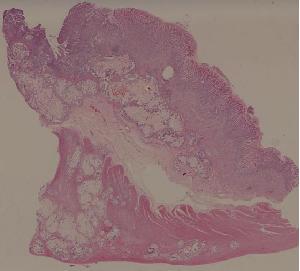

低倍视野

49. syphilitic aortitis

50. Labar pneumonia

51. Carnification of the lung

52. Lobular pneumonia

57. Carcinoma of the lung

59. Chronic atrophic gastritis

60. Gastric ulcer

61. Gastric adenocarcinoma(Mucinous adenocarcinoma of the stamoch)

62. Acute viral hepatitis (common type)

63.Chronic active viral hepatitis

64. Acute fulminant viral hepatitis

65. Subacute fulminant viral hepatitis

66. Active nodular cirrhosis of the liver

67. Inactive nodular cirrhosis of the liver

68. Biliary fibrosis

69. Hepatocellular carcinoma

72. Membranous glomerulonephritis

73. Acute glomerulonephritis

74. Crescentic glomerulonephritis

75. Chronic glomerulonephritis